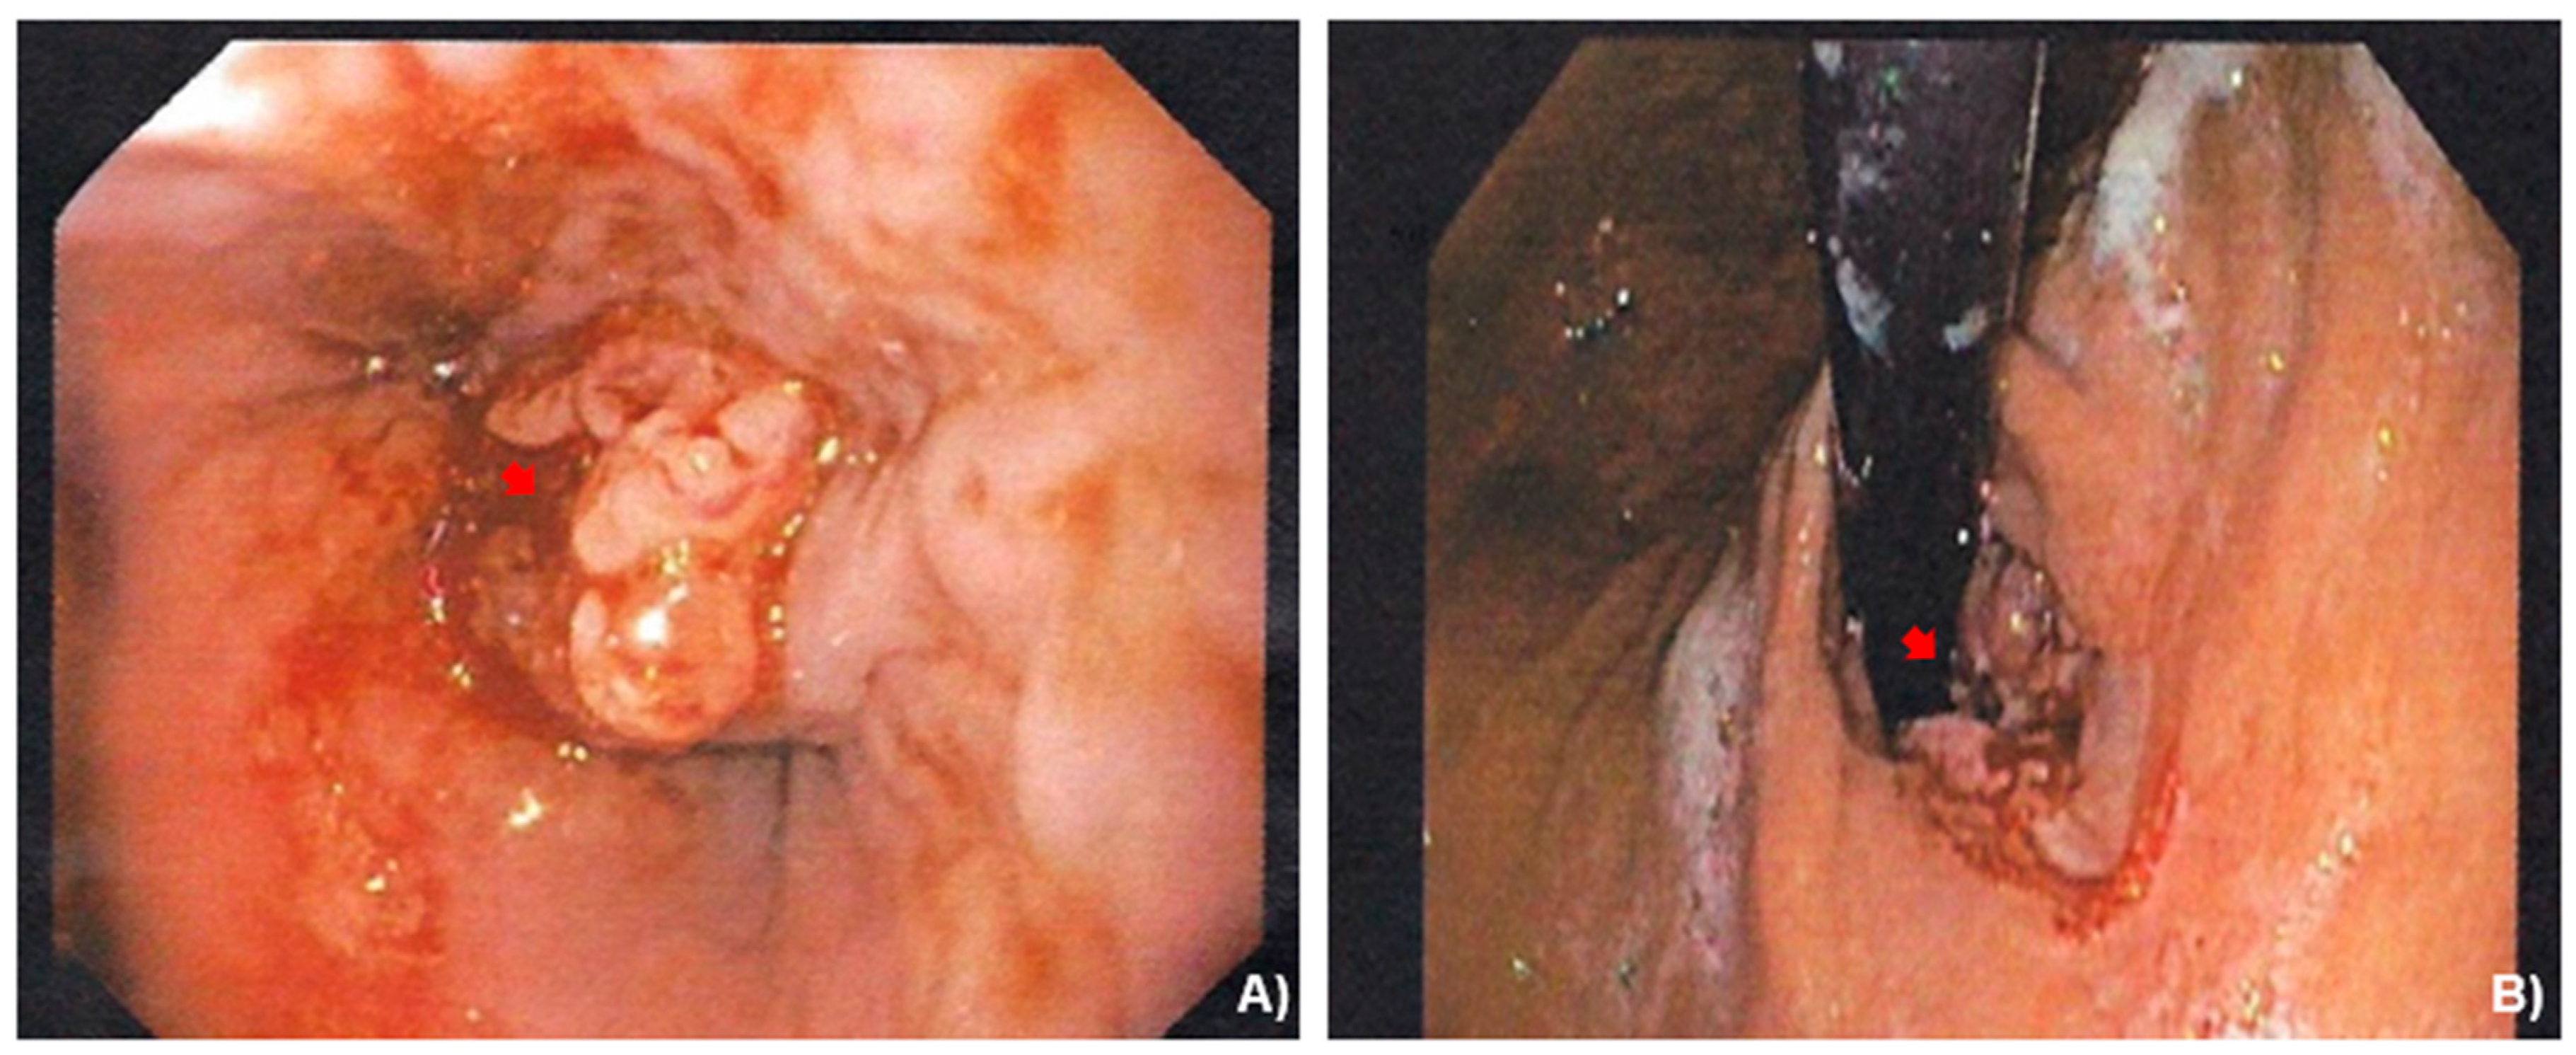

2.2. Case Presentation

3.1. Case Management